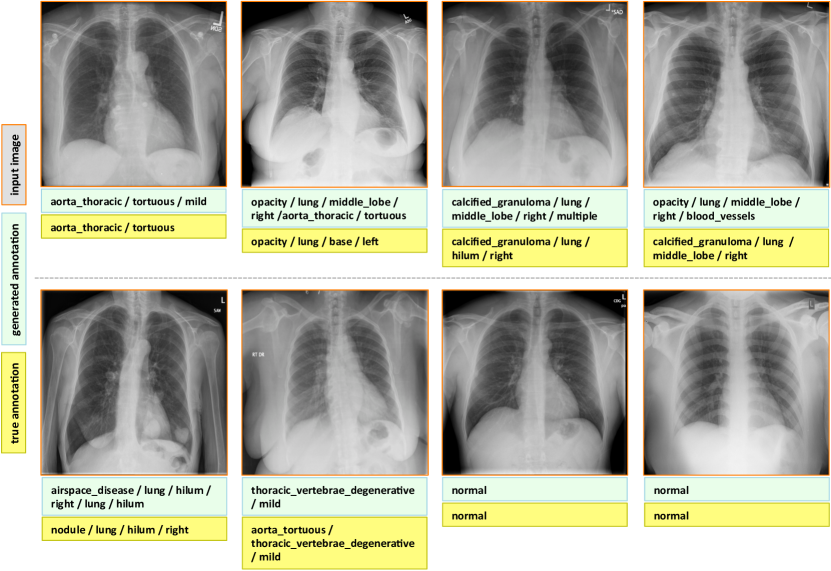

7.1 Evaluation

The final evaluated BLEU scores are provided in Table 5. We achieve better overall BLEU scores than those in Table 4 before using the joint image/text context. It is noticeable that higher BLEU-N () scores are achieved compared to Table 4, indicating that more comprehensive image contexts are taken into account for the CNN/RNN training. Also, slightly better BLEU scores are obtained using GRU on average and higher BLEU-1 scores are acquired using LSTM, although the comparison is empirical. Examples of generated annotations on the chest x-ray images are shown in Figure 6. These are generated using the GRU model, and more examples can be found in the supplementary material.

Appendix C More Annotation Generation Examples

More annotation generation examples are provided in Figures 10 and 11. Overall, the system generates promising results on predicting disease (labels) and its context (attributes) in the images. However, rare disease cases are more difficult to detect. For example, the cases pulmonary_atelectasis, spondylosis, and density (Figure 10), as well as foreign_bodies, atherosclerosis, costophrenic_angle, deformity (Figure 11) are much rarer in the data than calcified_granuloma, cardiomegaly, and all the frequent cases listed in Table 1 of the main paper.

Furthermore, the (left or right) location of the disease cannot be identified in a lateral view (obtained by scanning the patient from the side), as shown in Figure 11. Since our dataset contains a limited number of disease cases, we treat each x-ray image and report as a sample, and do not account for different views.